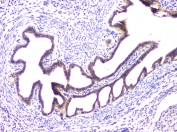

IHC staining of FFPE human ovarian cancer with RAB11B antibody at 1ug/ml. HIER: boil tissue sections in pH6, 10mM citrate buffer, for 10-20 min and allow to cool before testing.